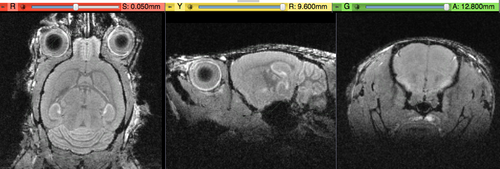

shown are, from left to right, panels of axial, sagittal and coronal views.

original, not RAS

original,after reorientation into RAS